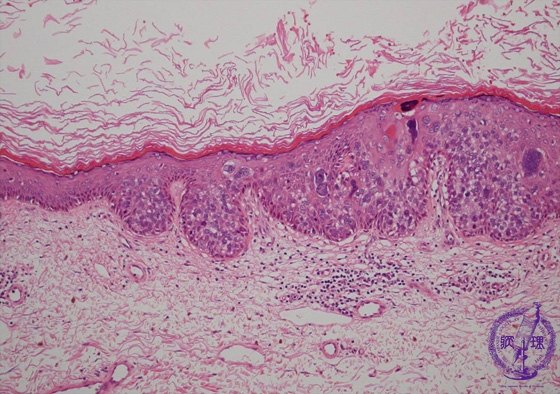

- ★(8)Squamous cell carcinoma(Bowen disease)

Microscopic findings: Bowen’s disease is one of the intraepidermal squamous cell carcinoma. It sometimes occurs with other internal malignancies.